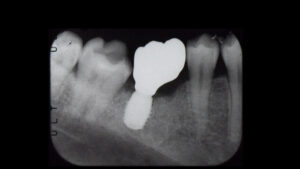

2023.05.12 奥歯1本 根が折れた奥歯をインプラントで治療した症例

| 処置内容・方法 | 抜歯してインプラントで治療した。 |

| 埋入箇所 | 下顎臼歯部 |

太い金属の土台によって根に大きな負担がかかり、かぶせものの下で縦に割れてしまっていることがわかりました。残念ですが歯が割れてしまうと残すことはできません。抜歯してインプラント治療をする計画を立てました。今回の場合は抜歯して一ヶ月弱骨の治癒を待ってインプラントオペを行うのが最善と診断し、抜歯をして6週待ちました。

歯茎を切開して骨の状態を確認します。

インプラント埋入のスペースを作ってインプラントが入りました。

適切な一次固定の確認をとり、仮歯まで作っていきます。

オペから8週でセラミックの歯の型取り、10週で全ての治療が終了しました。